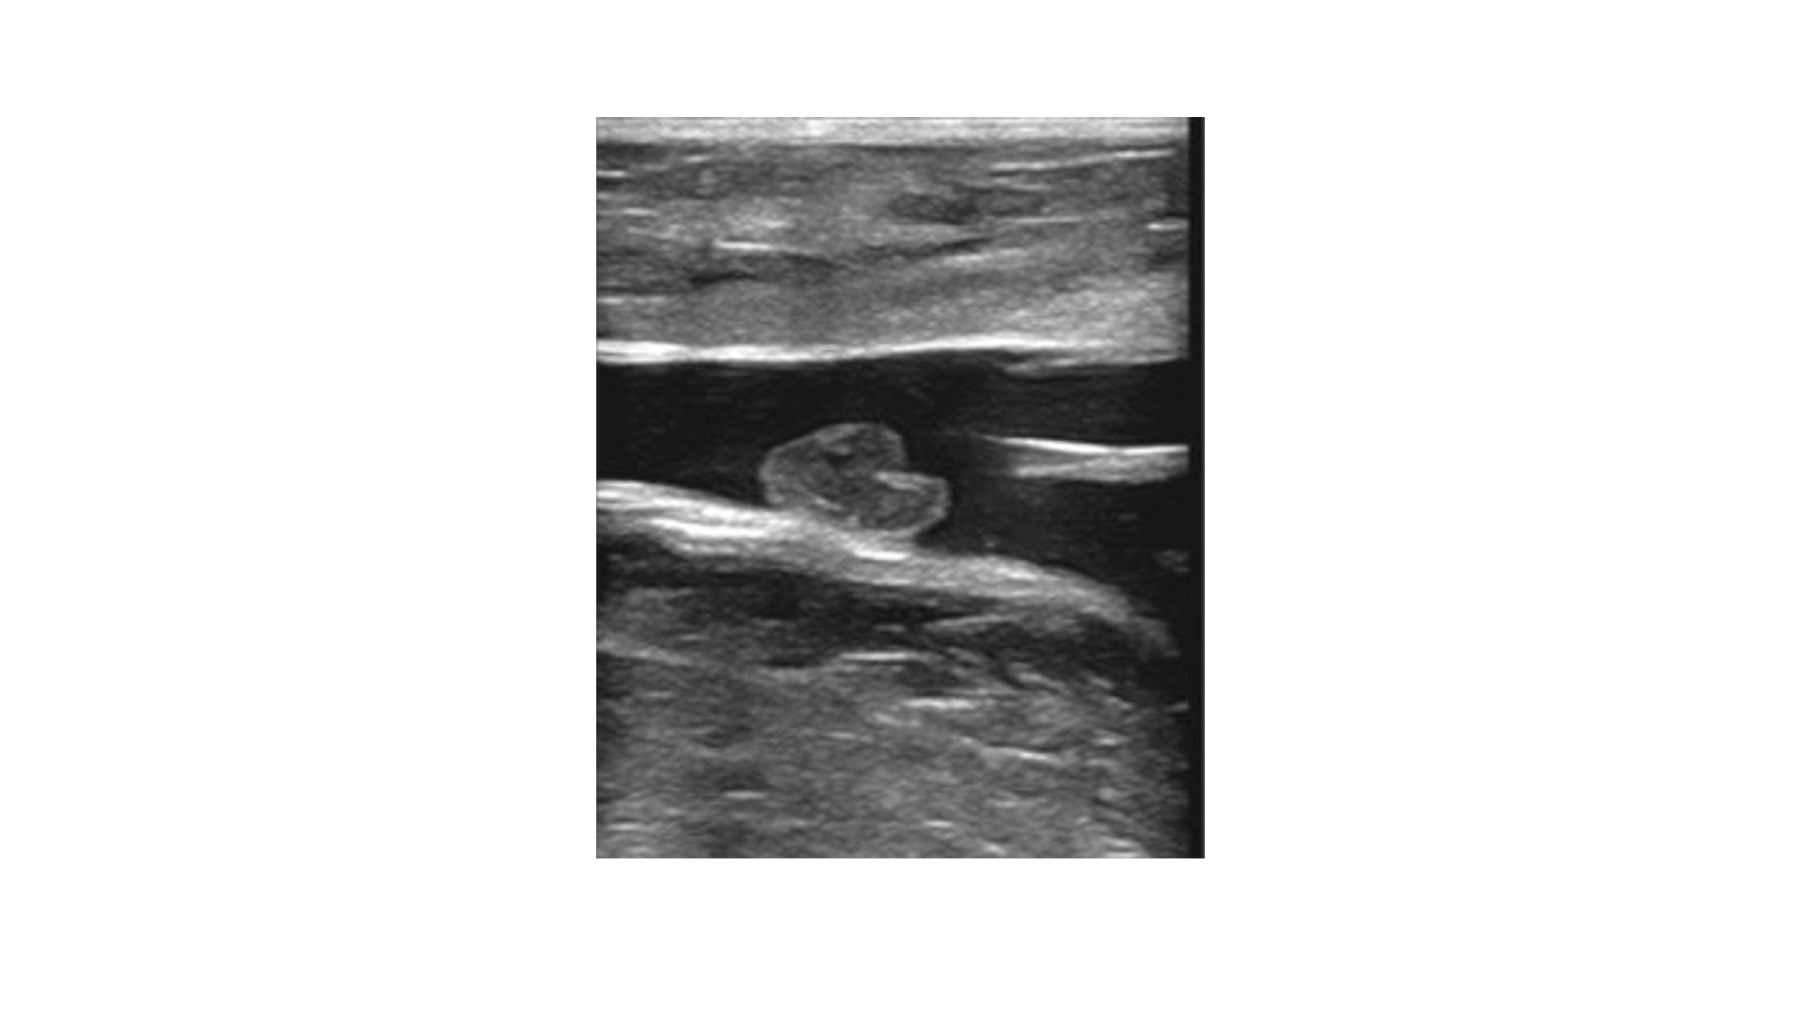

سۆنهری دوپلێکس